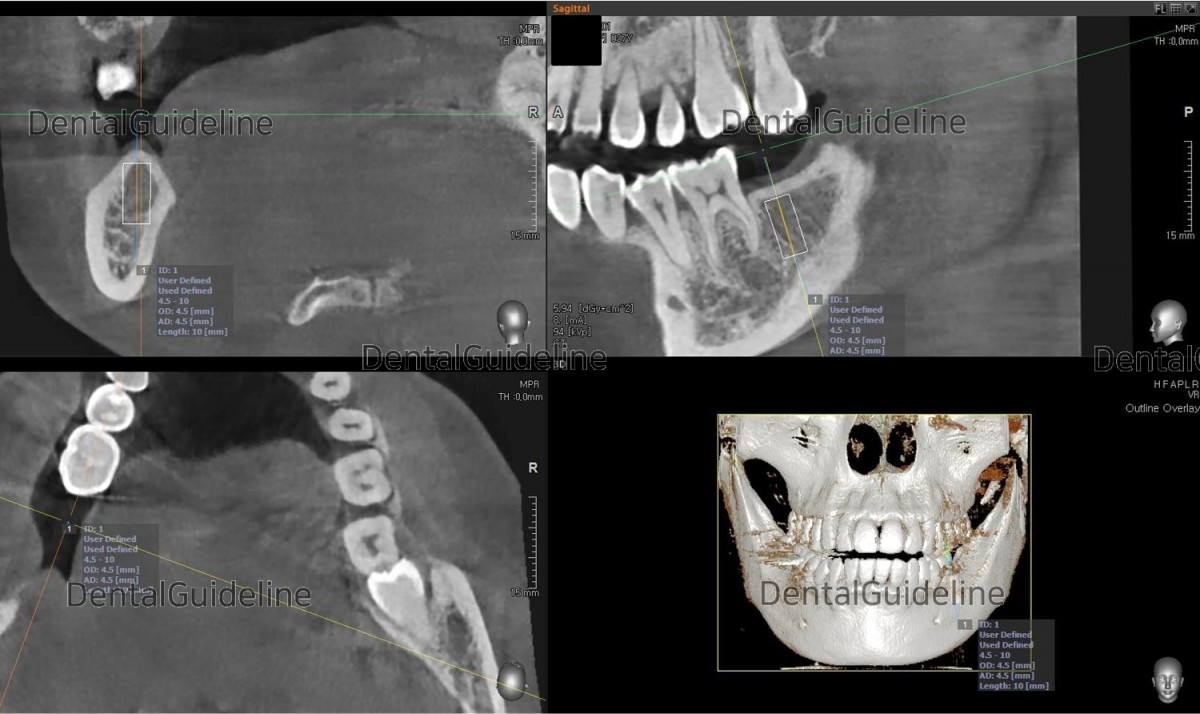

3. CBCT scan and simple surgical simulation.

5. Serial osteotomy and placement of the implant (Arum Dentistry Co. NB1 Ø4.5/L10, 30Ncm).

8. CBCT scan view